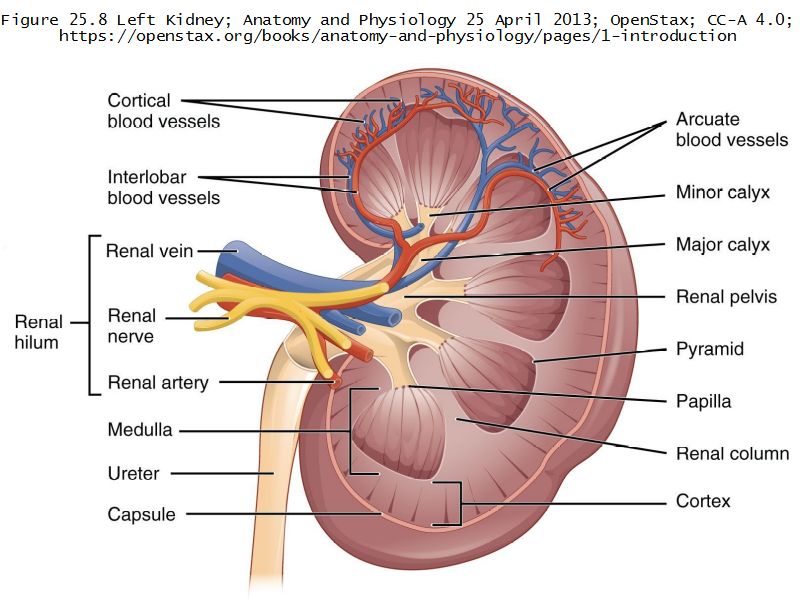

Kidney Objectives

- Basic anatomy of the kidney

- Make an annotated drawing of the macroscopic view of the kidney.

Kidney

- Capsule

- Cortex

- Medulla

- Multilobar

Multilobar

- Conical mass (pyramid)

- Medullary tissue

- capped with

- Cortex

- Delineated by

- Renal columns

- Apex of pyramid

- Papilla

- Projects into renal pelvis

Pyramid